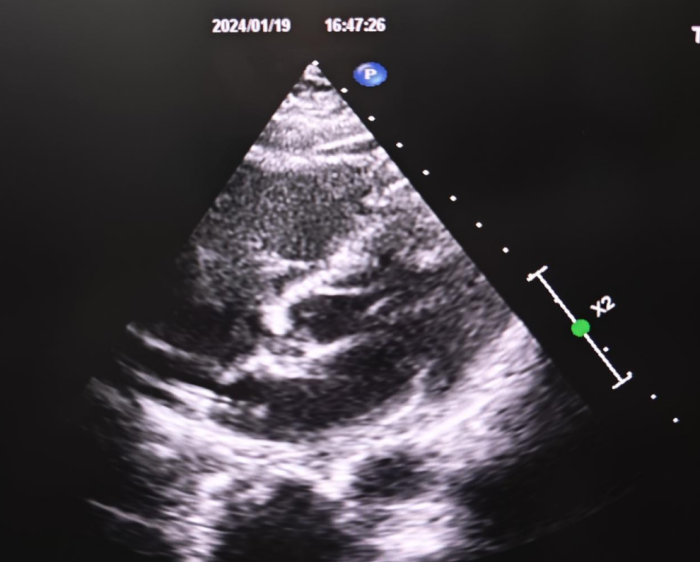

输送鞘进入左房